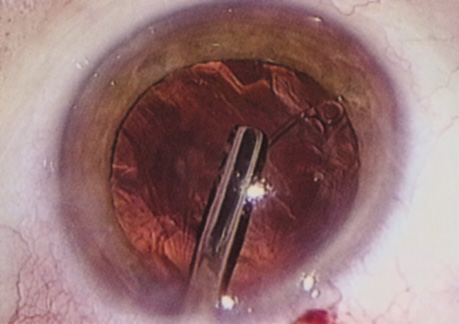

Capsulorrhexis can be performed with a cystitome, capsulorrhexis forceps, or combination-type instruments. Regardless of which instrument is used, several principles can help the surgeon successfully complete capsulorrhexis. It is important to maintain the anterior chamber, because making the chamber shallow increases tension on the zonules and causes the tear to run peripherally. The authors recommend the use of a viscoelastic agent for maintaining chamber depth and, of course, for endothelial protection. Therefore, if the tear begins to run peripherally, the surgeon should redeepen the anterior chamber before attempting to redirect the tear. Additionally, folding the capsule margin can aid the surgeon in redirecting the tear more accurately (Fig. 10).

Fig. 10. The capsulorrhexis tear is more easily redirected by folding the capsule over, in advance of the tear.